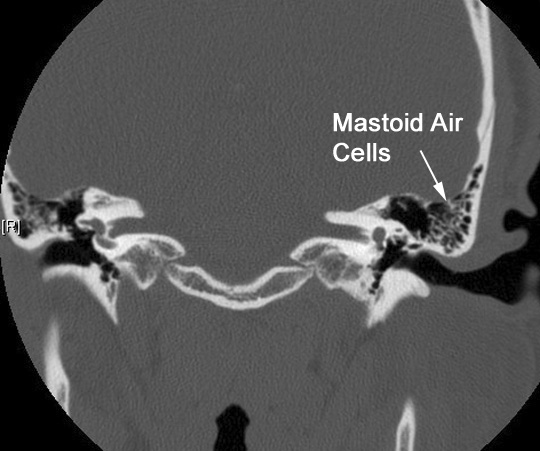

Identify mastoid air cells. Click the image for labeling.